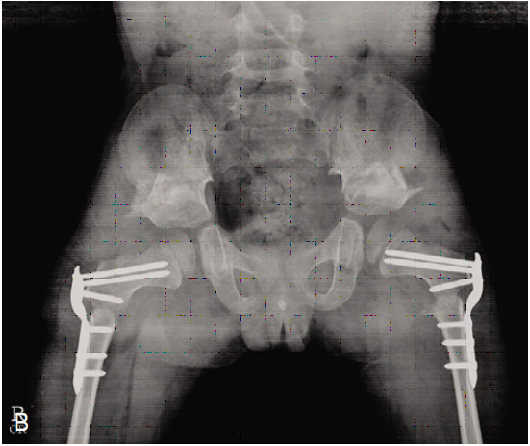

고관절 재건술

뇌성마비 환자에서 고관절 아탈구 및 탈구가 발생하는 경우가 있으며 이로 인하여 통증이 발생하고 앉는자세 유지가 어려우며 청결유지에 문제가 발생할 수 있습니다. 따라서 뇌성마비 환자는 고관절에 대한 정기적인 검진이 필요합니다.

고관절 아탈구나 탈구가 발생한 경우 표준적인 방법으로 관혈적 정복술, 대퇴 내반 감염 절골술, 골반골 절골술을 동시에 시행하게 됩니다.

| 수술 전 |

수술 후 |